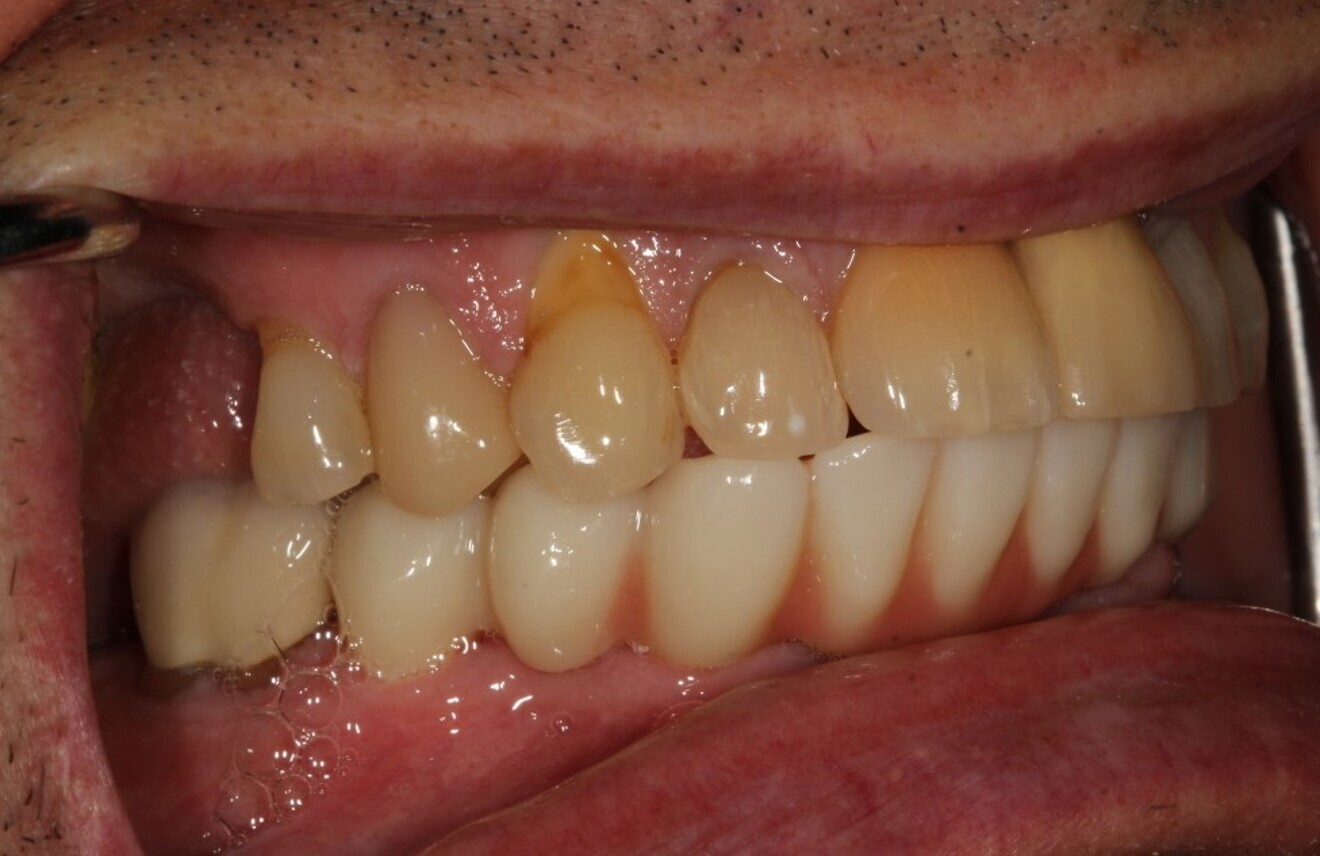

Figs. 18a & b: Final restoration in function.

A final full-arch zirconia restoration was manufactured, and the final seating was verified with radiographs (Fig. 17) and cemented with PANAVIA SA Cement Universal (Kuraray Noritake Dental). The patient returned two weeks later for an occlusion check and adjustment along with an oral hygiene check. Pink firm gingiva around all the implants was noted such that it was even difficult to get a probe into the sulcus (Fig. 18).